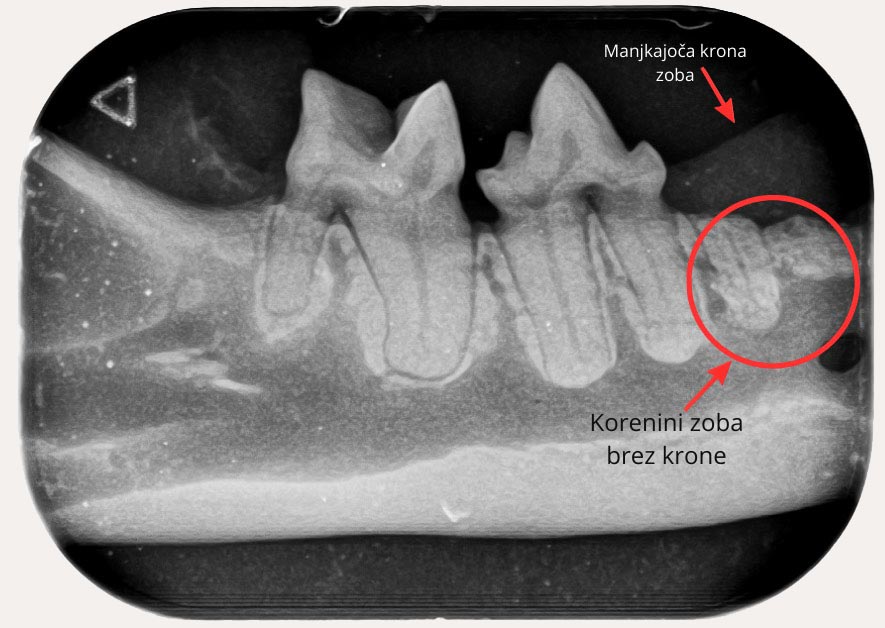

Del zoba, ki ga vidimo v gobcu, se imenuje krona. Predstavlja del zoba, med tem ko je preostanek skrit in ni viden. Zobje se razlikujejo po velikosti, obliki in številu korenin. Kljub temu imajo nekaj skupnega. Zob lahko navzven deluje zdrav, v notranjosti pa je lahko poškodovan ali vnet.

Če takšnega zoba ne zdravimo, lahko žival občuti nelagodje in bolečino. Težave se lahko stopnjujejo. S prostim očesom ne moremo oceniti celotnega stanja zoba. Zato je nujna uporaba zobnega rentgena (zobni RTG). Ta omogoča slikanje vsakega zoba posebej.

Na podlagi slike dobimo celosten vpogled v stanje zoba. Tako določimo naslednji korak. Če se odločimo za ekstrakcijo, po puljenju ponovno uporabimo zobni RTG. Tako preverimo, ali je korenina v celoti odstranjena.

Pri poškodovanih koreninah se pogosto zgodi, da se med ekstrakcijo zdrobijo. To s prostim očesom pogosto ni vidno. Če ostanki ostanejo v dlesni, lahko povzročijo nove zaplete. Med njimi so kronična vnetja, trajna bolečina in nastanek fistul.

Sodobne smernice poudarjajo, da je zobni RTG pri stomatološkem posegu nujen. Veterinarji se pogosto srečujemo z željami lastnikov, ki želijo hitro puljenje majavega zoba. Toda tak pristop je zastarel. Pregled z zobnim RTG je minimalni strokovni standard. Ekstrakcije brez zobnega RTG-na ga ne dosegajo več.